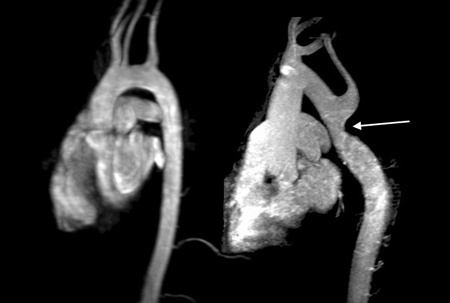

Ressonância nuclear magnética (RNM) cardíaca revelando arco aórtico normal em formato de bengala à esquerda, comparado com uma coarctação aórtica não diagnosticada anteriormente, imediatamente após a origem da artéria subclávia esquerda (seta), detectada por RNM em uma mulher adulta com síndrome de Turner com hipertensão grave dos membros superiores

Do acervo pessoal de Carolyn Bondy, MS, MD (estudo do National Institutes of Health [NIH])